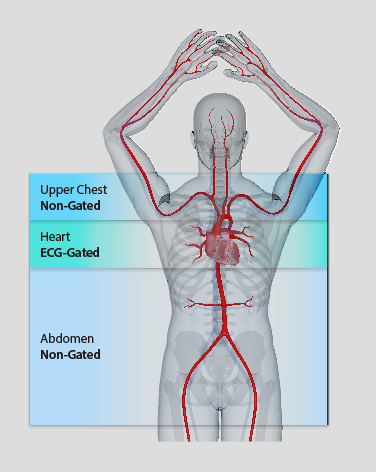

Технология vHP3 позволяет объединять несколько специализированных исследований в рамках одного сканирования.